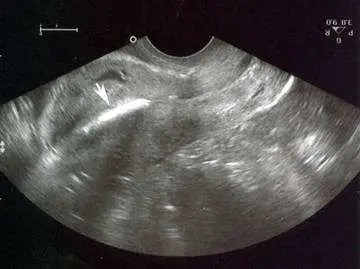

一位 26 歲生過三胎之年輕婦女因不正常陰道出血而就醫,其婦科史有裝置子宮避孕器三年。理學檢查經陰道診視發現子宮頸表面平滑,血液自子宮頸口處流出,子宮頸口未見有子宮避孕器之尾巴線;觸診發現子宮大小正常且無觸壓痛之情形。經陰道超音波掃描子宮之情形如下圖,箭頭所指之最適合診斷為:

經陰道超音波影像可見子宮腔內有一線狀高回音結構(linear echogenic structure),後方伴有聲影(posterior acoustic shadowing)。此強回音線性結構位於子宮腔中軸,走向符合 IUD 莖部(stem)的解剖位置。IUD 因其金屬/高密度材質,在超音波下呈現特徵性的強回音信號,伴隨明顯的後方聲影,此為超音波診斷 IUD 位置的標準所見。子宮內膜本身未見明顯增厚或局灶性病灶,未見液體積聚(排除 hematometra 的可能)。此超音波影像正是教科書上「IUD 位於子宮腔內」的典型表現,解釋了為何臨床上找不到 IUD 尾巴線——尾巴線可能已縮入子宮頸管內,但 IUD 本體仍在子宮腔。